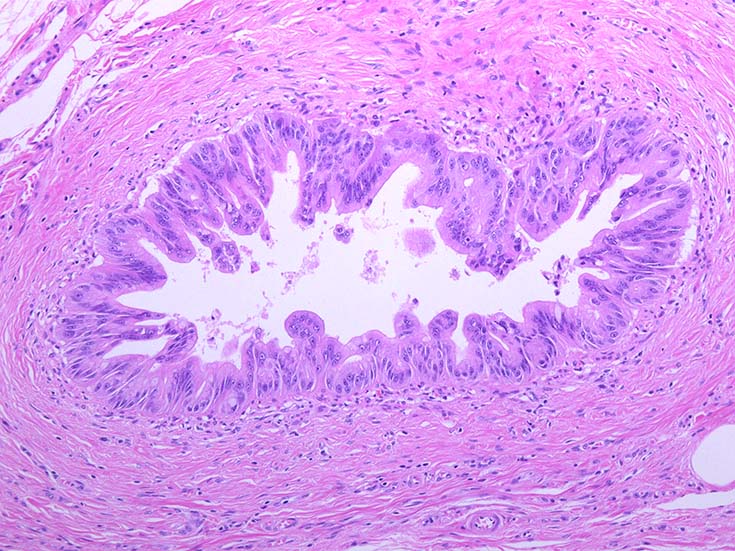

膵上皮内腫瘍性病変 pancreatic intraductal neoplasm(PanIN)*16

Low-grade PanINとhigh-grade PanINの分類

high-grade PanIN

PanINの図譜はJohns Hopkins The Sol Goldman Pancreatic Cancer Research CenterのHome page*19から引用.

2. PanIN-2, PanIN-3;

• TP53の不活化--PanINでのIHCでは機能喪失が,PanIN3のみで観察される. 膵癌発がん過程の遅い段階に出現する事象.

浸潤性膵癌では, 50-75%で不活化.

• SMAD4の不活化--PanIN3の30%で発現陰性化. PanIN-1,2では, SMAD4免疫染色は陽性. 発現の陰性化は後期PanINで発現する重要な異常*20.

浸潤性膵管癌では, 55%で不活化.

• BRCA2(DNA修復に重要な遺伝子)の不活化--PanINではPanIN3に特異的なイベント. germ line変異は浸潤性膵管癌の7~10%に認められる.

• cyclinD1過剰発現--PanIN1ではまれ, PanIN-2では29%, PanIN-3では57%と膵癌発がん過程に伴って頻度が上昇する遺伝子変化.

• COX-2の過剰発現--悪性腫瘍では, 細胞増殖, 生存, 浸潤および, 血管新生に関与. 正常膵管,PanIN-1では発現が低く, PanIN2から過剰発現頻度が高くなる.